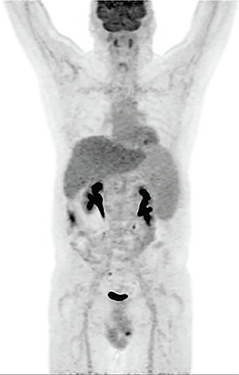

The mechanism of localization of 67Ga-citrate is not well understood but has been postulated to reflect iron metabolism. 67Ga-citrate has a half-life of 78 hours, is cyclotron produced, and decays by electron capture, with the critical organ being the colon. Its photopeaks are 93, 185, 300 and 394 keV. Given the long half-life, this agent is not recommended for pediatric patients. Historically, 67Ga-citrate has been used for the imaging of lymphoma, which occasionally helps in the incidental detection of other tumors. In the past, 67Ga-citrate was the preferred agent for the study of sarcoidosis, which is now better evaluated with 18F-fluorodexyglucose (18F-FDG) positron emission tomography (PET). In addition, 67Ga-citrate could be used in the setting of vertebral osteomyelitis since it has better overall performance, however, 67Ga-citrate is falling out of favor due to its long half-life, relatively high radiation dose, and unfavorable imaging characteristics (1, 2). Figure 1 shows normal biodistribution of 67Ga-citrate.

Fig 1

Figure 1 Normal distribution of 67Ga-citrate. Anterior and posterior planar images of the head, neck, chest, abdomen, pelvis and proximal lower extremities demonstrate normal biodistribution of 67Ga-citrate.